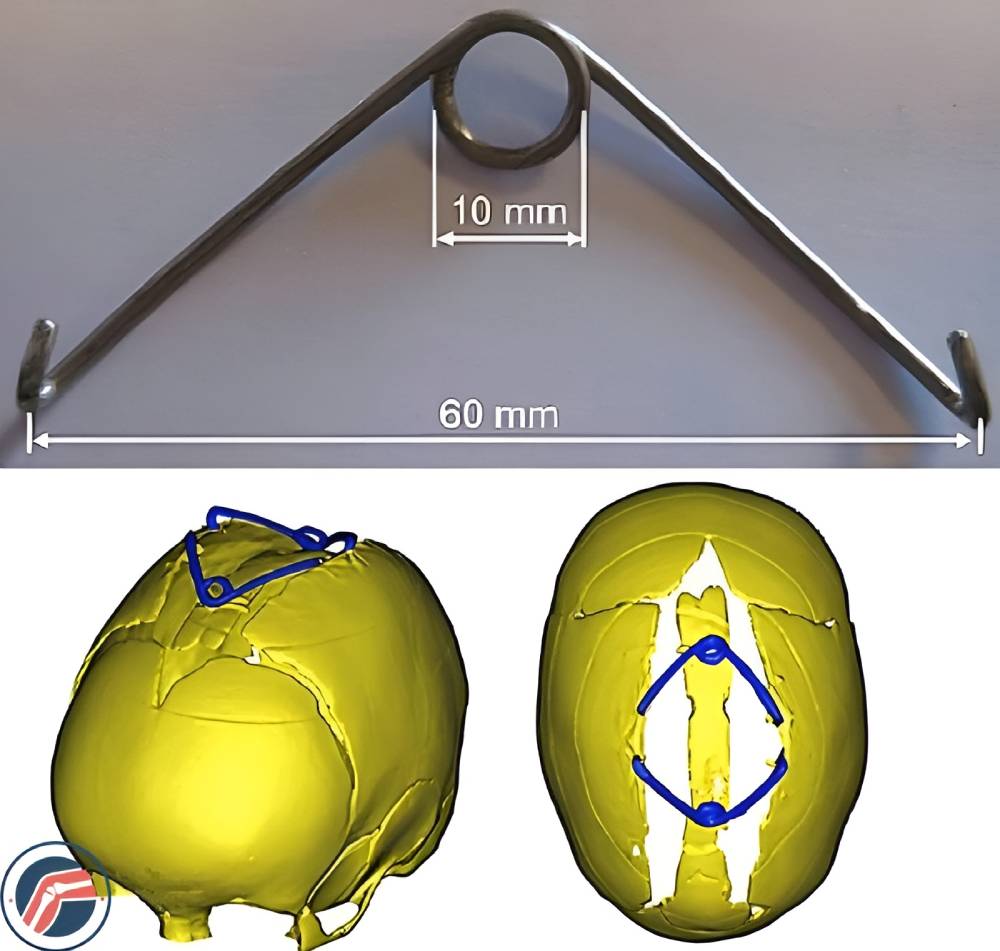

فنرهای جمجمهای: این جراحی با کرانیکتومی نواری شروع میشود، جایی که جراح درز بسته شده را باز میکند و پس از آن، جراح فنرهای فولادی ضد زنگ را در درز تازه باز شده قرار میدهد. این کار به مغز فضای رشد میدهد. بعد از چند ماه، جراح فنرها را خارج میکند.

از این روش معمولا برای درمان سینوستوز ساژیتال استفاده میشود.